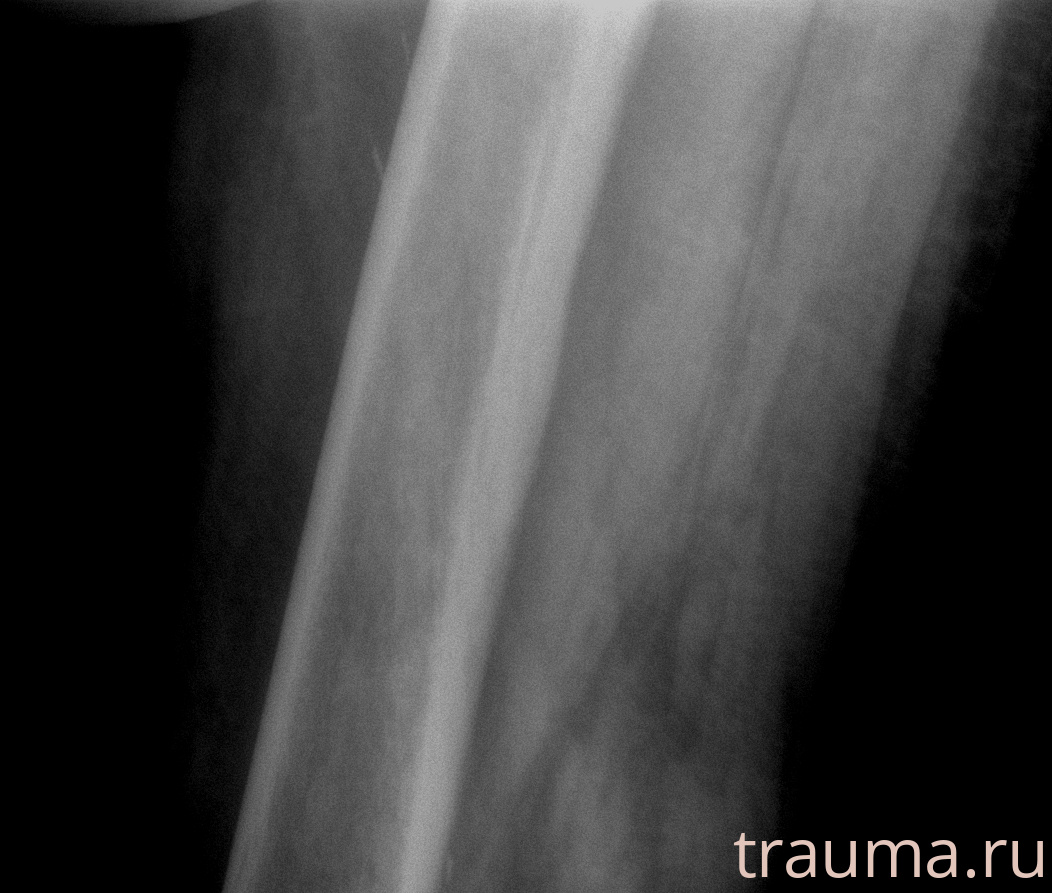

Рентгенограммы

Рентген на дому: по вашему адресу приезжает врач-рентгенолог, травматолог-ортопед с мобильным рентгеновским аппаратом, проводит диагностику травмы или заболевания, делает необходимые рентгенограммы, дает рекомендации по дальнейшему лечению. Получить качественные снимки в домашних условиях возможно благодаря уникальной методике, разработанной МосРентген Центром для института  Склифосовского